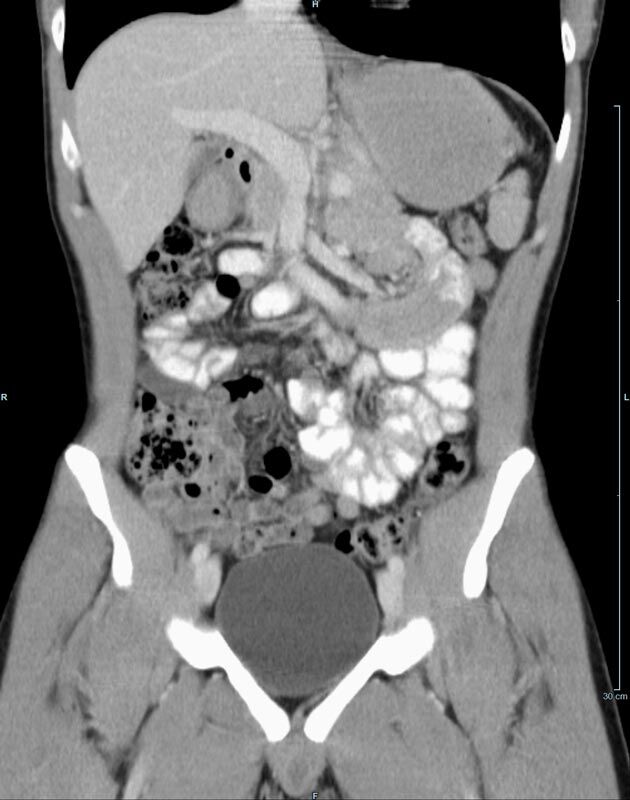

Kopf

• Schlaganfalldiagnostik

• Traumadiagnostik (Akutdiagnostik nach Verletzungen, Unfällen)

• Nasennebenhöhlen (Entzündungen, Tumore)